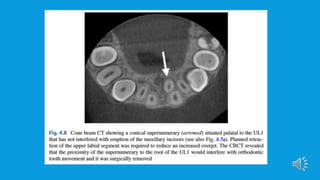

 Routine radiographs such as dental panoramic radiographic, upper standard

occlusal and long-cone periapical can be used in combination to localize a

supernumerary tooth using the parallax technique (horizontal or vertical tube

shift) and may give sufficient information to allow safe removal.

However, if the proximity to developing roots is a concern, assessment of

resorption is required or a decision to whether orthodontic tooth movement

can go ahead without removal of supernumerary tooth, then CBCT may be

indicated.This additional imaging technique has shown to enhance the ability

to localize a supernumerary.